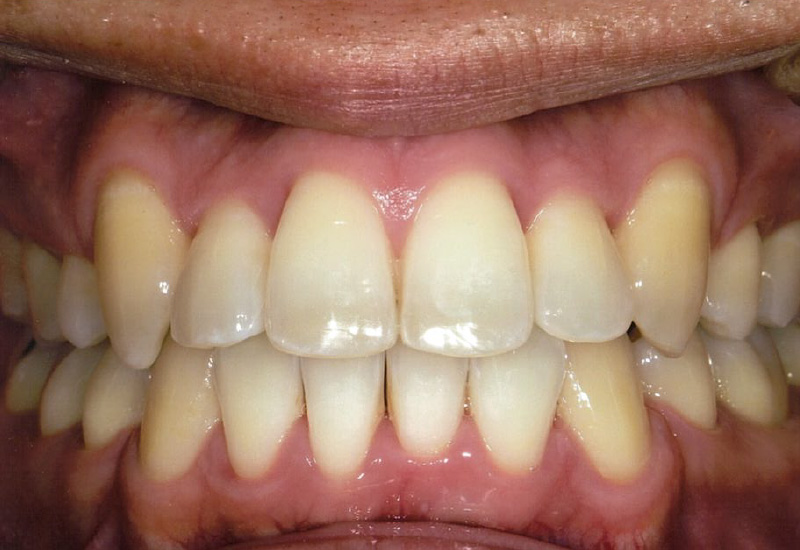

Case3 / 八重歯・ガタガタ

治療前

治療後

| 主訴 | 八重歯・歯のガタつき・顎の不調和による噛み合わせの乱れ |

|---|---|

| 治療内容 | 3D-LST矯正治療法を用い適切に歯を移動。見た目だけでなく、噛みやすさや顎の安定感も向上 |

| 患者年代・治療期間 | 30代男性・4年4ヶ月(難治症例) |